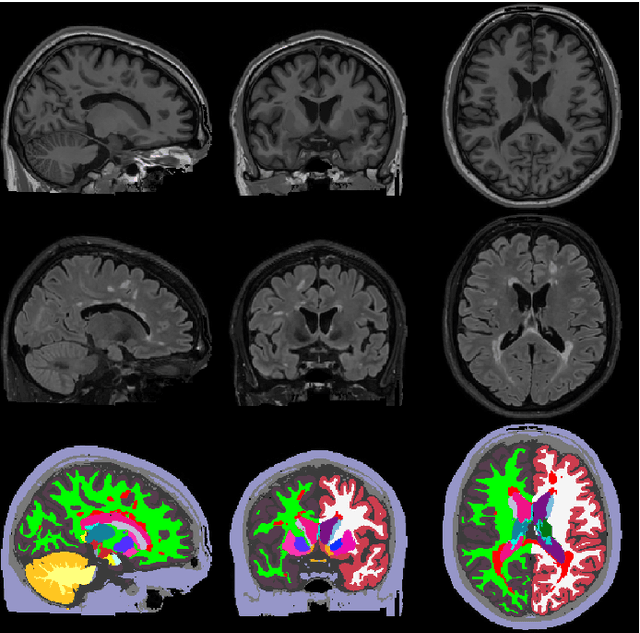

Abstract:Here we present a method for the simultaneous segmentation of white matter lesions and normal-appearing neuroanatomical structures from multi-contrast brain MRI scans of multiple sclerosis patients. The method integrates a novel model for white matter lesions into a previously validated generative model for whole-brain segmentation. By using separate models for the shape of anatomical structures and their appearance in MRI, the algorithm can adapt to data acquired with different scanners and imaging protocols without retraining. We validate the method using three disparate datasets, showing state-of-the-art performance in white matter lesion segmentation while simultaneously segmenting dozens of other brain structures. We further demonstrate that the contrast-adaptive method can also be applied robustly to MRI scans of healthy controls, and replicate previously documented atrophy patterns in deep gray matter structures in MS. The algorithm is publicly available as part of the open-source neuroimaging package FreeSurfer.